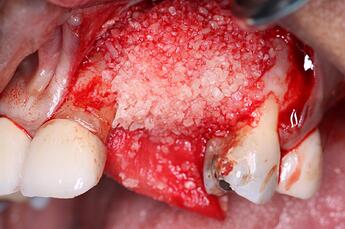

The first part of our grafting technique involved placement of DALI Cortical Cancellous Graft and initial placement of OsseoSeal Collagen Membrane. Notice how we position the membrane to tuck it under the palatal flap to help build up the bone graft. (for additional information on this technique see: Placement Techniques for OsseoSeal Porcine Collagen Membrane and Using OsseoSeal for Buccal Contour Augmentation )